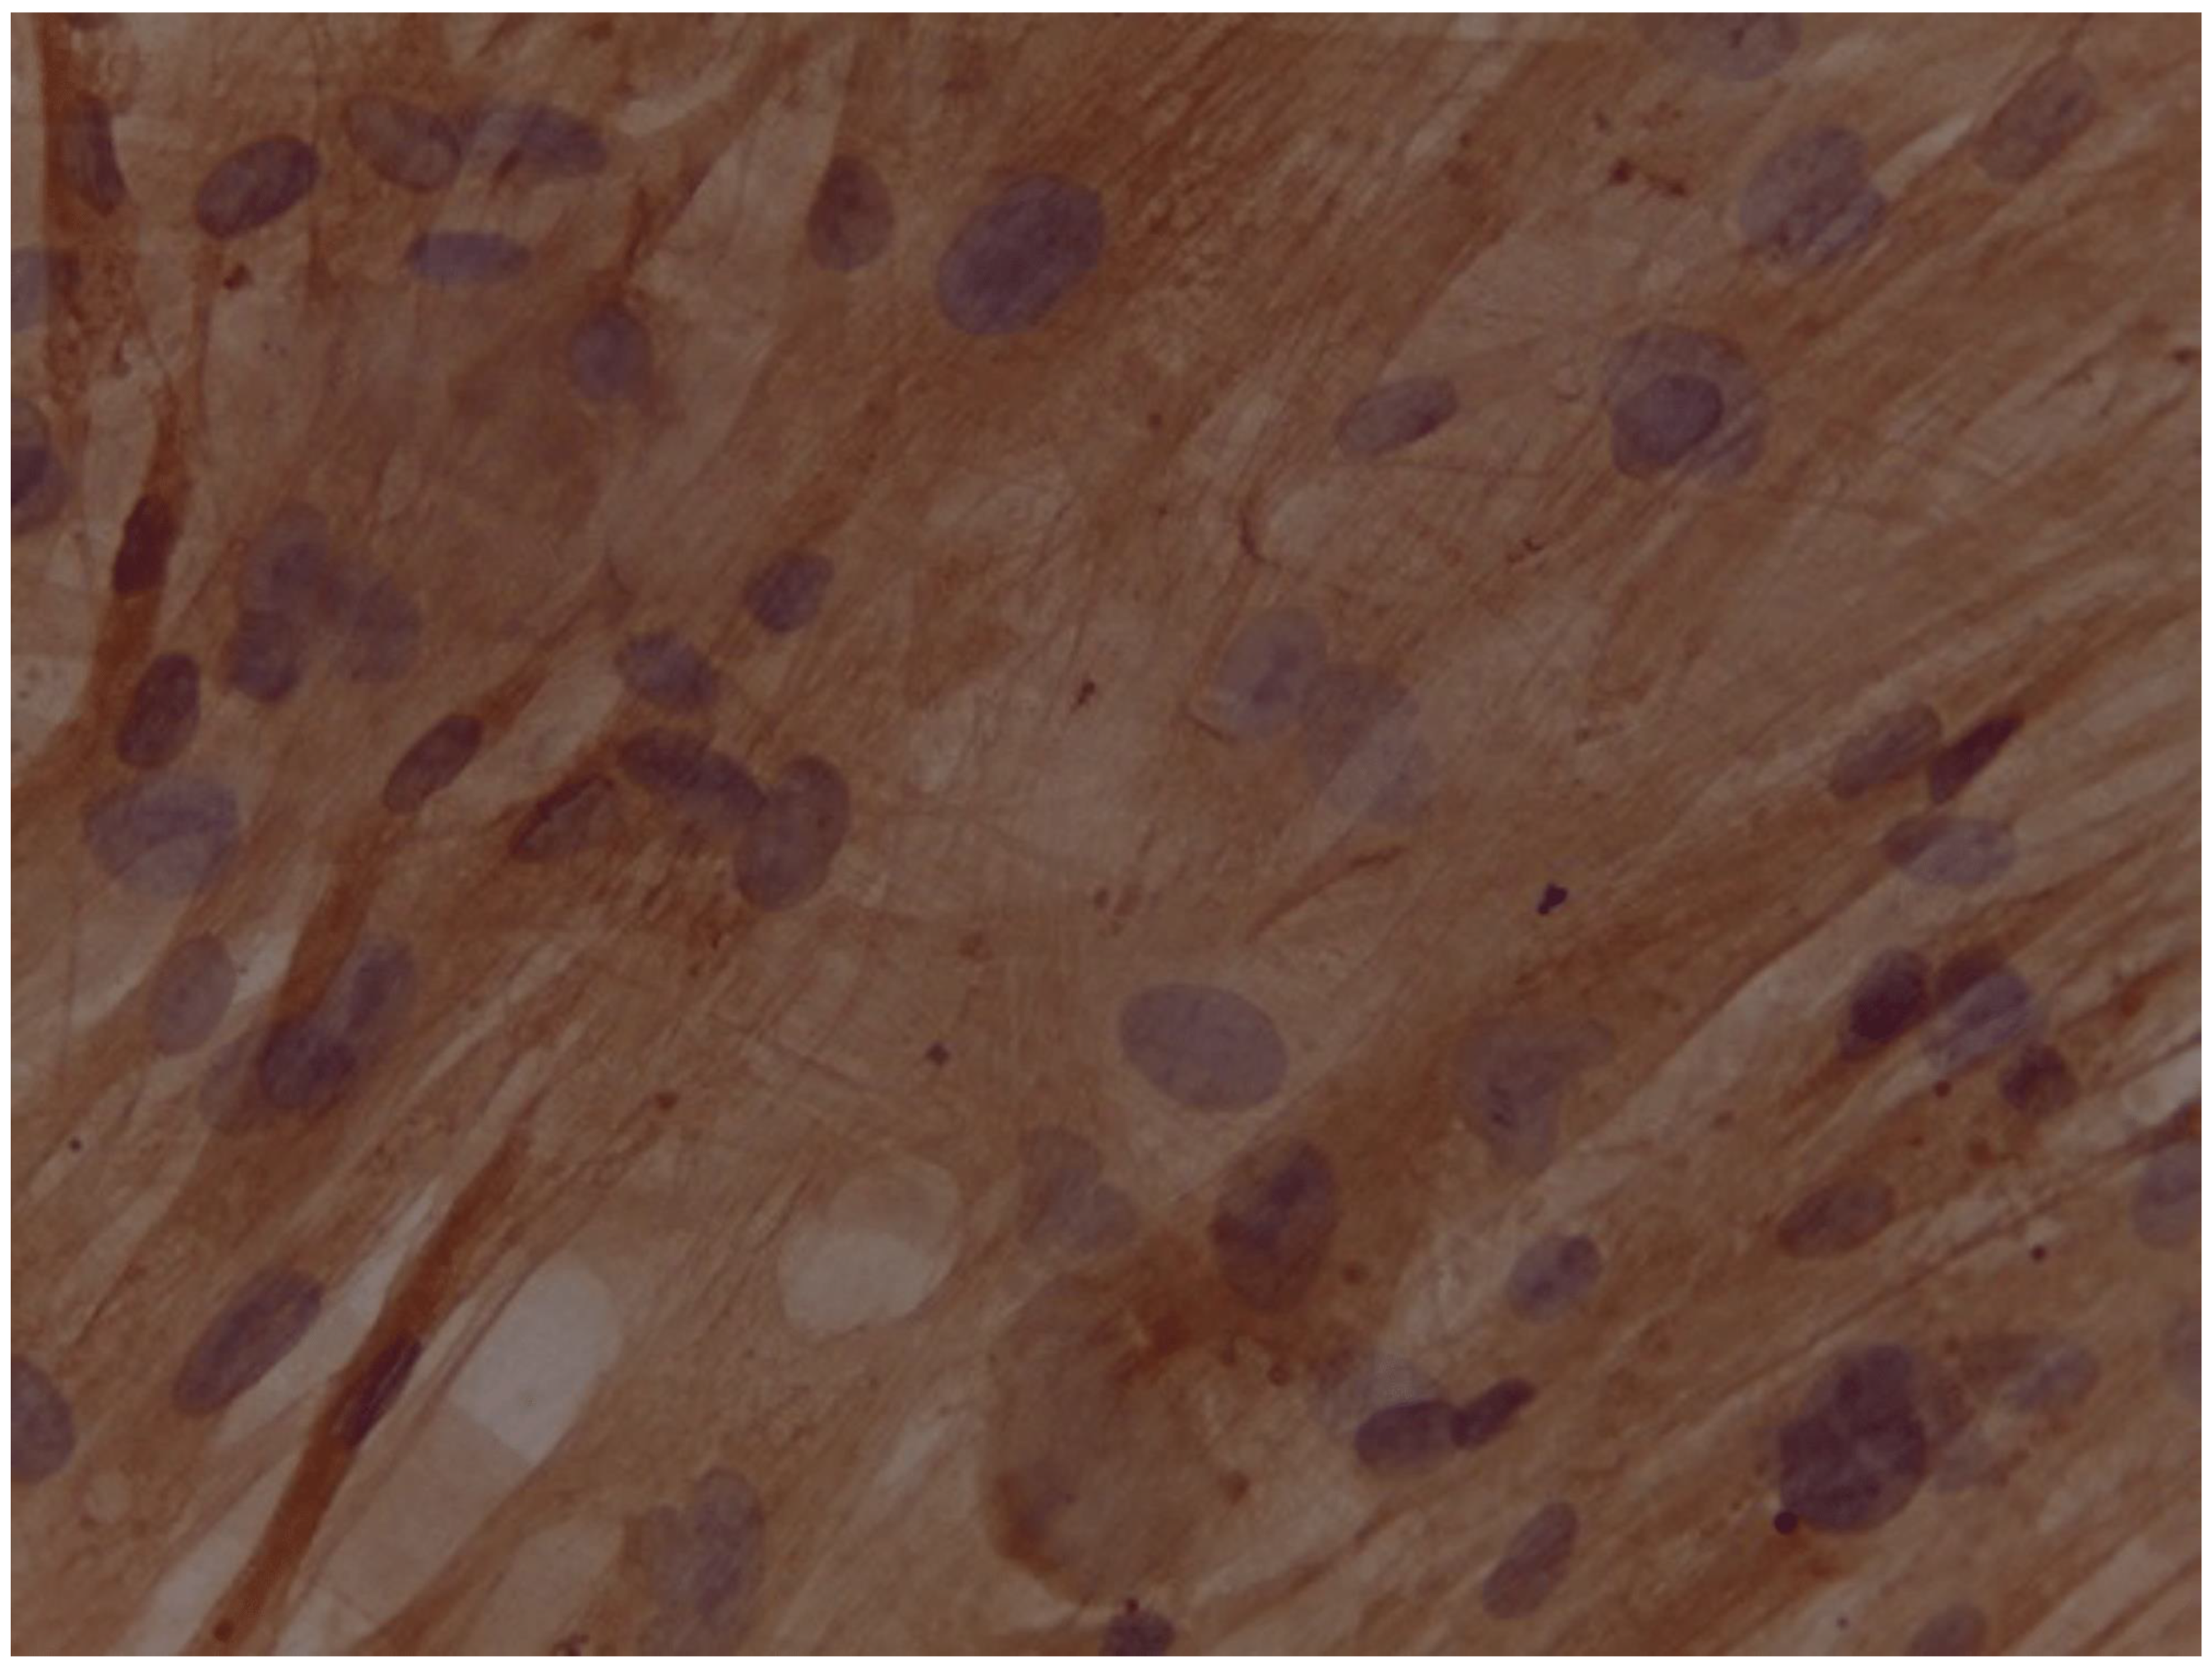

Assessment of expression of cardiomyocyte-like cells differentiation marker Troponin by Immunocytochemistry